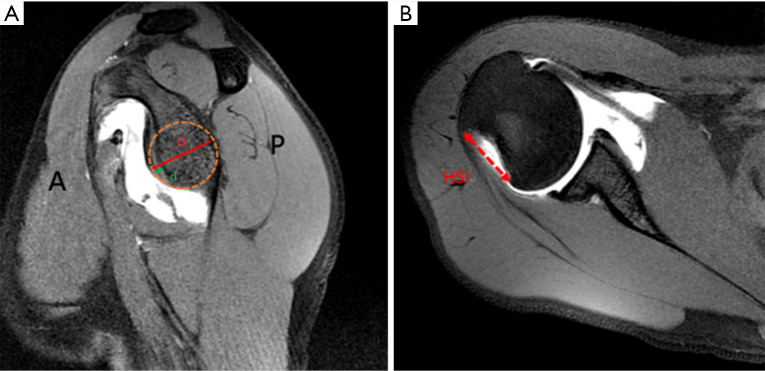

Key content and findings: ASI typically occurs from abduction and external rotation forces. Diagnosis relies on clinical assessment and imaging (magnetic resonance imaging or computed tomography), to evaluate soft tissue and bony injuries. Non-operative management is associated with high recurrence rates in contact athletes. Surgical options include arthroscopic Bankart repair (ABR) with or without remplissage, open Bankart repair (OBR), or bone block procedure such as Latarjet procedure or distal tibia allograft. All of which have been shown to decrease risk of recurrence and have a high rate of return to sport. The choice of procedure depends on the extent of soft tissue and bony involvement and the athlete's individual demands. ABR with glenoid bone loss >13.5% have high recurrence rates, therefore, additional procedures such as remplissage or bone block procedures should be considered.

Conclusions: ASI in the contact athlete is a common and challenging injury to manage. Surgical intervention provides superior outcomes in terms of stability and recurrence prevention compared to non-operative management of ASI in the contact athlete. Patient-specific considerations including level of sport, patient goals, and timing of season are considerations for treatment. Labral injury with <13.5% of glenoid bone loss and on-track Hill-Sachs lesion ABR is recommended, labral injury with 13.5-20% of glenoid bone loss with off-track Hill-Sachs lesion ABR with remplissage or OBR with capsule shift is recommended, and if >20% then bone block procedure is recommended.